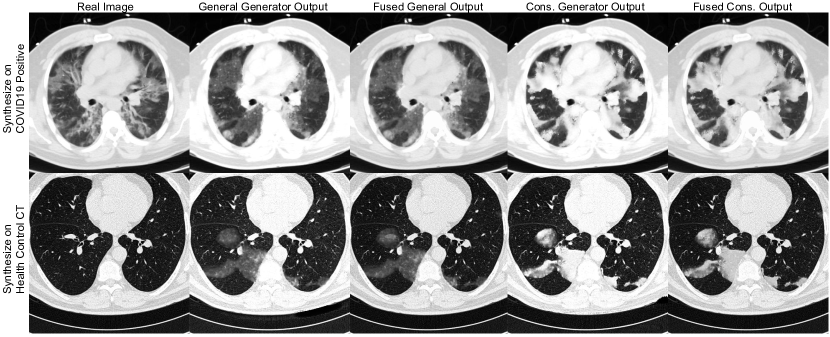

Refer to caption

Figure 3: Example axial slices to illustrate the visual difference in different synthesis settings. From left to right: the original image; the model output from the generator trained with all the COVID-19 positive images; The output of fusing the generator output in the second column with the original image; The output of the generator trained with only high-intensity abnormalities; The output of fusing the model in the fourth column and the original image. The first row is obtained by inpainting the patterns on-to a COVID-19 patient using the same mask manually annotated. The second row is obtained by generating the COVID-19 patterns on-to a control CT using a synthetic mask.